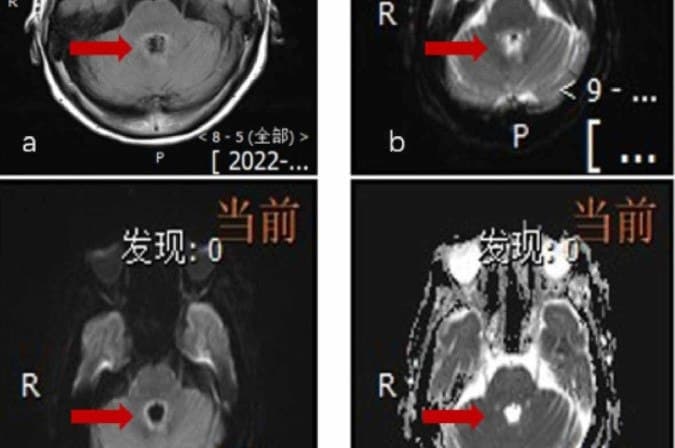

Estudos médicos sobre infecções intracranianas por B. mandrillaris, revelam apenas 10 sobreviventes entre mais de 150 casos relatados em todo o mundo. (Foto: reproduçao/Revista Científica Heliyon)

A chinesa deu entrada no hospital em 2022 com tonturas e fraqueza. Os primeiros exames mostraram lesões no cérebro, então os médicos suspeitaram inicialmente de um tumor metastático. Após nove dias internada e piora no quadro, a equipe médica fez uma punsão lombar, em que foi diagnosticado a encefalite amebiana balamuthia, (B. mandrillaris). Apesar das medidas agressivas de tratamento, o estado da paciente piorou rapidamente.